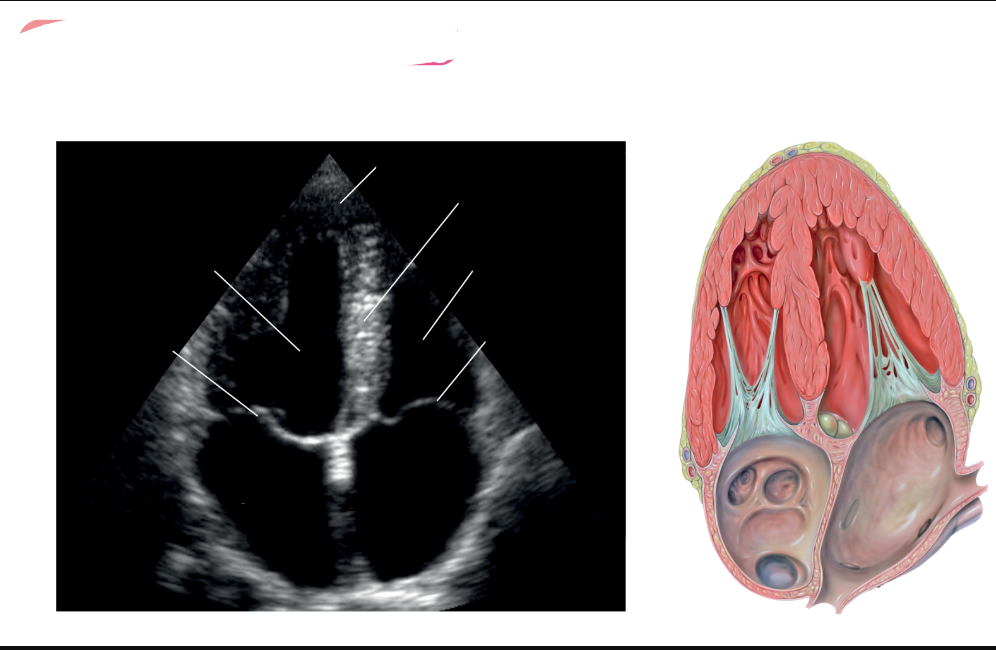

What view is this

label red